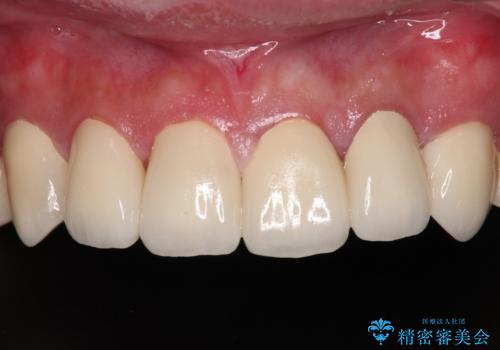

むし歯は多かったものの、歯肉の腫脹はそれほどなかったため、最小限の治療回数で治療を終えることができました。